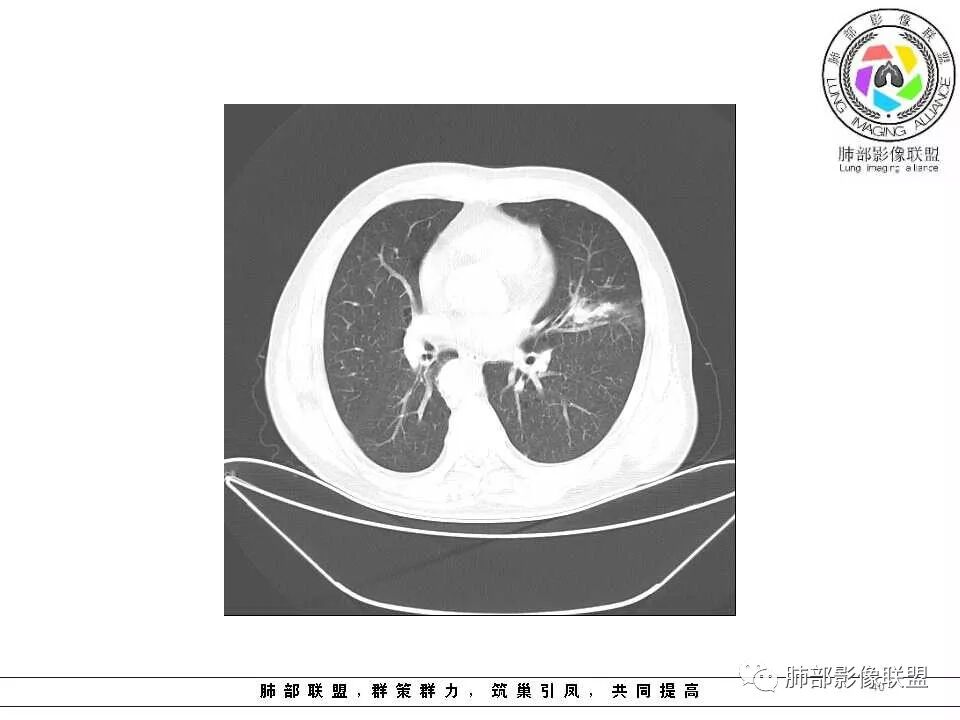

影像学特点:肺气肿背景下在大概一年的时间里出现了一个光滑的小结节,因为图像给的不是太薄,与支气管的关系判断不清,从结节周围出现斑片状炎症来判断,应该考虑结节位于支气管内,周围是阻塞性炎症,这样比较容易解释咯血

左肺上叶光滑结节影 似乎与支气管没有关系  ,给的纵隔窗病灶中心似乎点状钙化  病灶旁有更小结节,与上一年片比较 结节增大明显  考虑恶性 类癌可能

老年男性,有咳血病史,左肺上叶舌段一年时间出现新发类圆形小结节,感觉在支气管内,部分凸出气管外,没有mpr不好说,远端肺野斑片模糊影,考虑阻塞性炎症,纵隔无明显肿大淋巴结,小细胞代排,按照发展速度,类癌低度恶性,应该发展缓慢,一年病史,代排,首先考虑鳞癌并阻塞性炎症

肺气肿背景,2016年左肺上叶上舌段见微结节,2017年5月左肺结节增大,密度均匀,边缘光滑锐利,与邻近血管关系密切,血管贴壁走行,外侧见尖状突起,下舌段片状影,沿着支气管走行,内有粘液栓,考虑鳞癌,鉴别小细胞肺癌。

左肺上叶舌段支气管管壁略增厚 间隔一年 管壁增厚明显 向腔外突出形成结节 管腔闭塞 远端片状及斑片影 纵隔淋巴结增大 肺气肿背景 考虑鳞癌伴阻塞性炎症可能

老年男性,咯血1月,肺气肿背景,16年左肺上叶舌段结节,左肺门疑似淋巴结肿大,呈结节感。17年左肺上叶舌段见沿支气管走行分布结节 远端阻塞性肺炎,左肺门淋巴结肿大明显,首先考虑恶性病变,鳞癌?类癌?

前次片2016年4月20相应位置就有小点状病灶,2017-5-15呈结节影改变,边界膨隆,远端阻塞炎性改变,考虑肺癌,鉴别炎性结节!

老年男性,咯血1月,肺气肿背景,左肺上叶舌段见沿支气管走行分布结节,呈葫芦样改变,左肺门淋巴结肿大明显,首先考虑恶性病变,小细胞癌可能